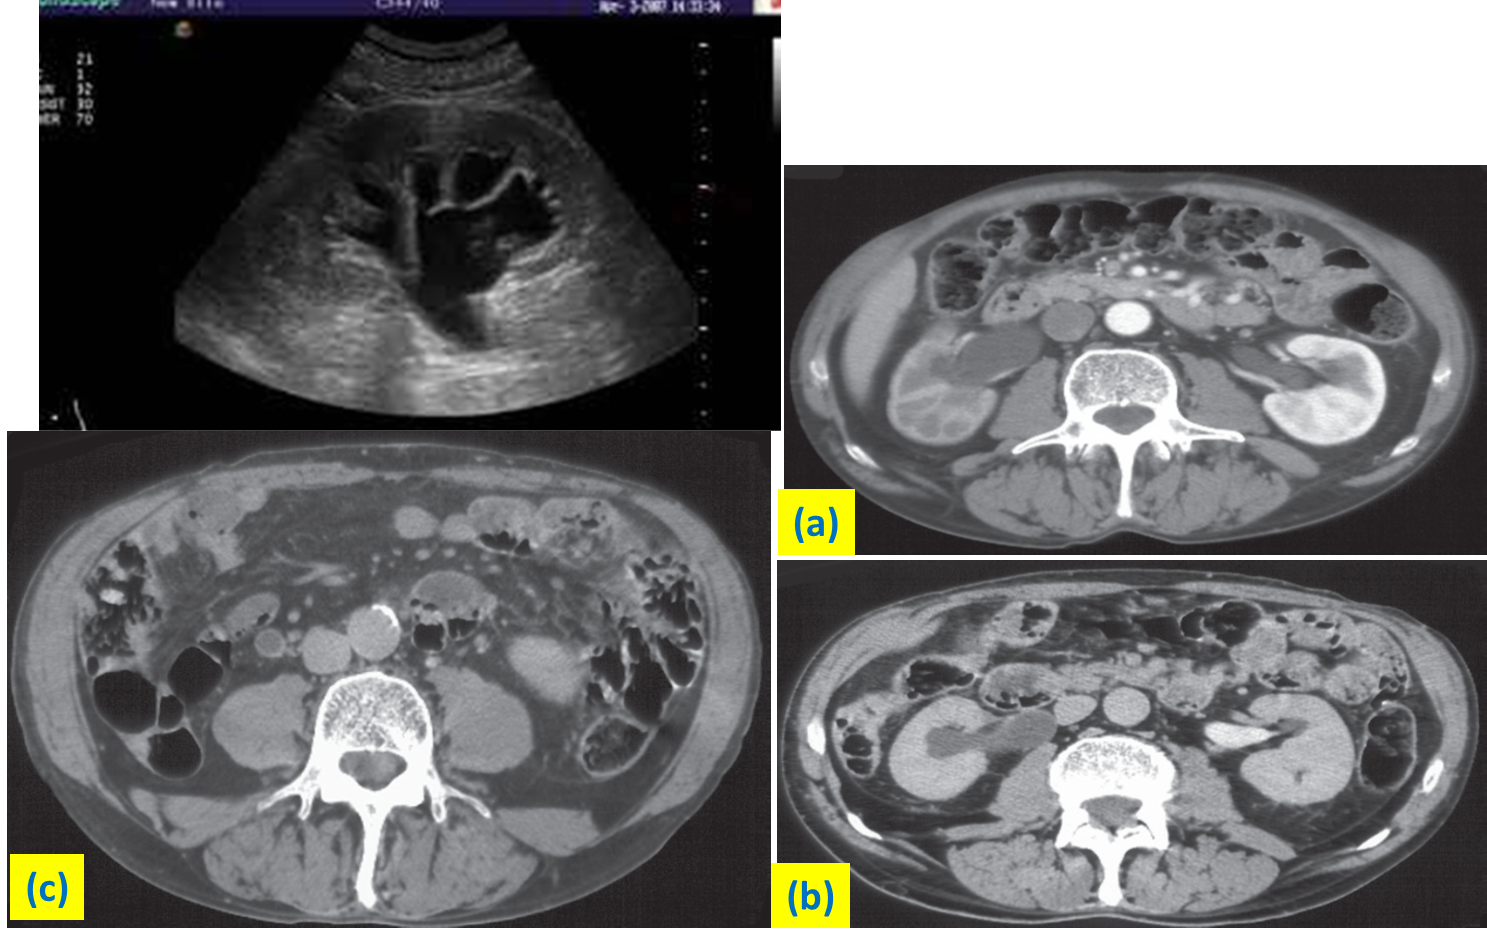

Ultrasound and CT images of hydronephrosis

(a) CT at the corticomedullary phase of enhancement. There is obstruction of the right kidney with dilatation of the pelvicaliceal system (b) CT at the delayed phase of enhancement. Intravenous contrast is seen in the left renal pelvis but not in the obstructed right renal pelvis. (c) CT through the dilated right ureter , in the same patient as (a) and (b).